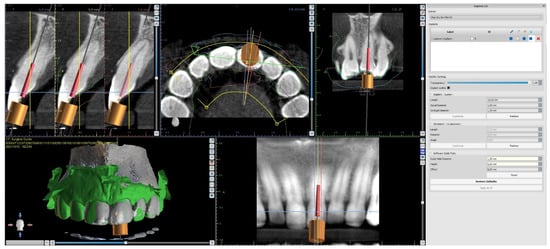

The upper arch was scanned with an intraoral scanner (PrimeScan, Dentsply Sirona) instead of analogue impressions. The STL file of the upper arch and the CBCT images were combined in Blue Sky Plan (Blue Sky Bio). The accuracy of the merging was cross-checked in three dimensions (Figure 9). An individual virtual implant with a diameter of 1.5 mm was used during planning, in accordance with the diameter of the endodontic access tool (Figure 10). The CBCT images allowed us to plan the position of the virtual implant so that the drill apex was located at the top of the visible part of the root canal system [23] (Figure 11).

Figure 10. Figure presenting settings of custom implant in Blue Sky Plan software. Implant length, guide tube height, and offset must be equal to access tool’s working length.

Figure 11. CBCT image presenting a scheduled virtual implant: endodontic access path in (a) sagittal view and (b) coronal view. The volume of the preserved dentin around the access path is shown.